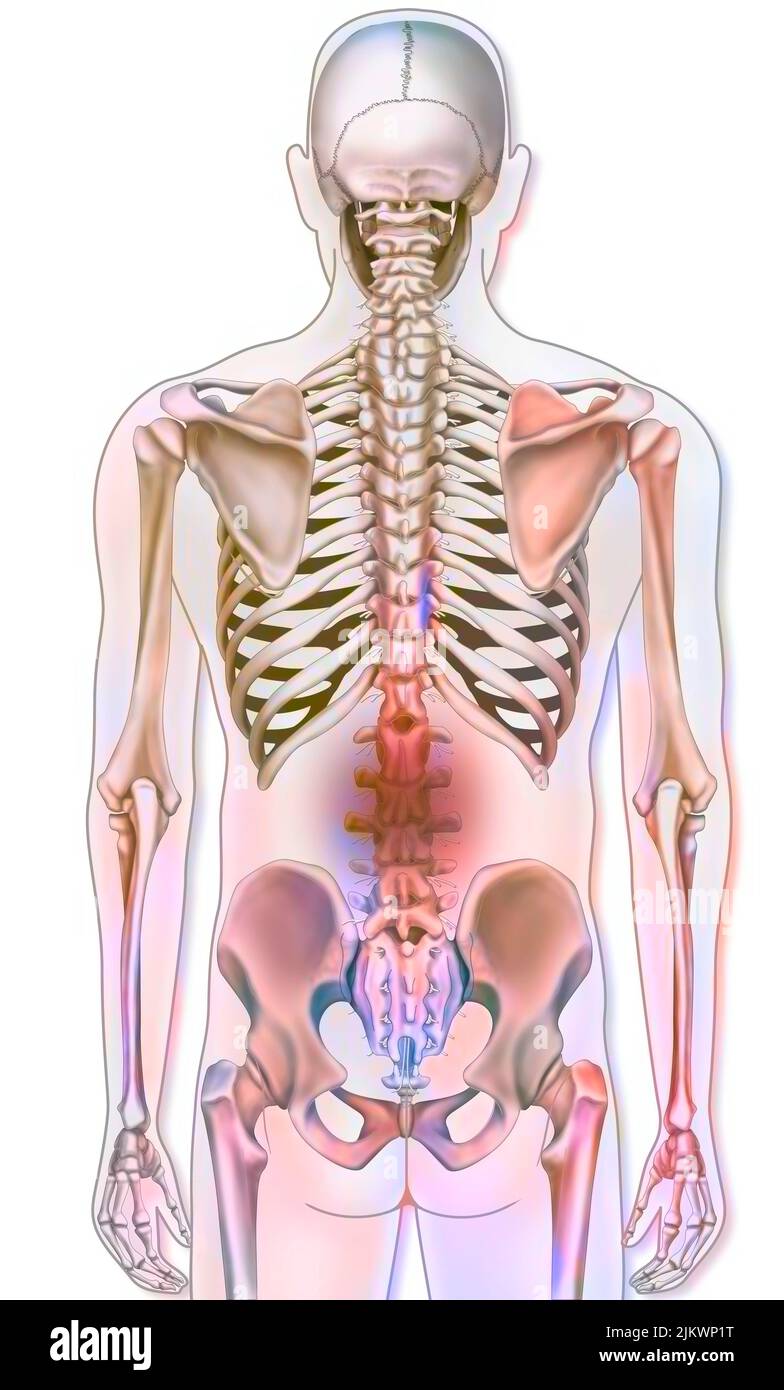

Knochensystem: Menschliches Skelett mit Darstellungen von Lendenschmerzen. Stockfotohttps://www.alamy.de/image-license-details/?v=1https://www.alamy.de/knochensystem-menschliches-skelett-mit-darstellungen-von-lendenschmerzen-image476924500.html

Knochensystem: Menschliches Skelett mit Darstellungen von Lendenschmerzen. Stockfotohttps://www.alamy.de/image-license-details/?v=1https://www.alamy.de/knochensystem-menschliches-skelett-mit-darstellungen-von-lendenschmerzen-image476924500.htmlRF2JKWP1T–Knochensystem: Menschliches Skelett mit Darstellungen von Lendenschmerzen.